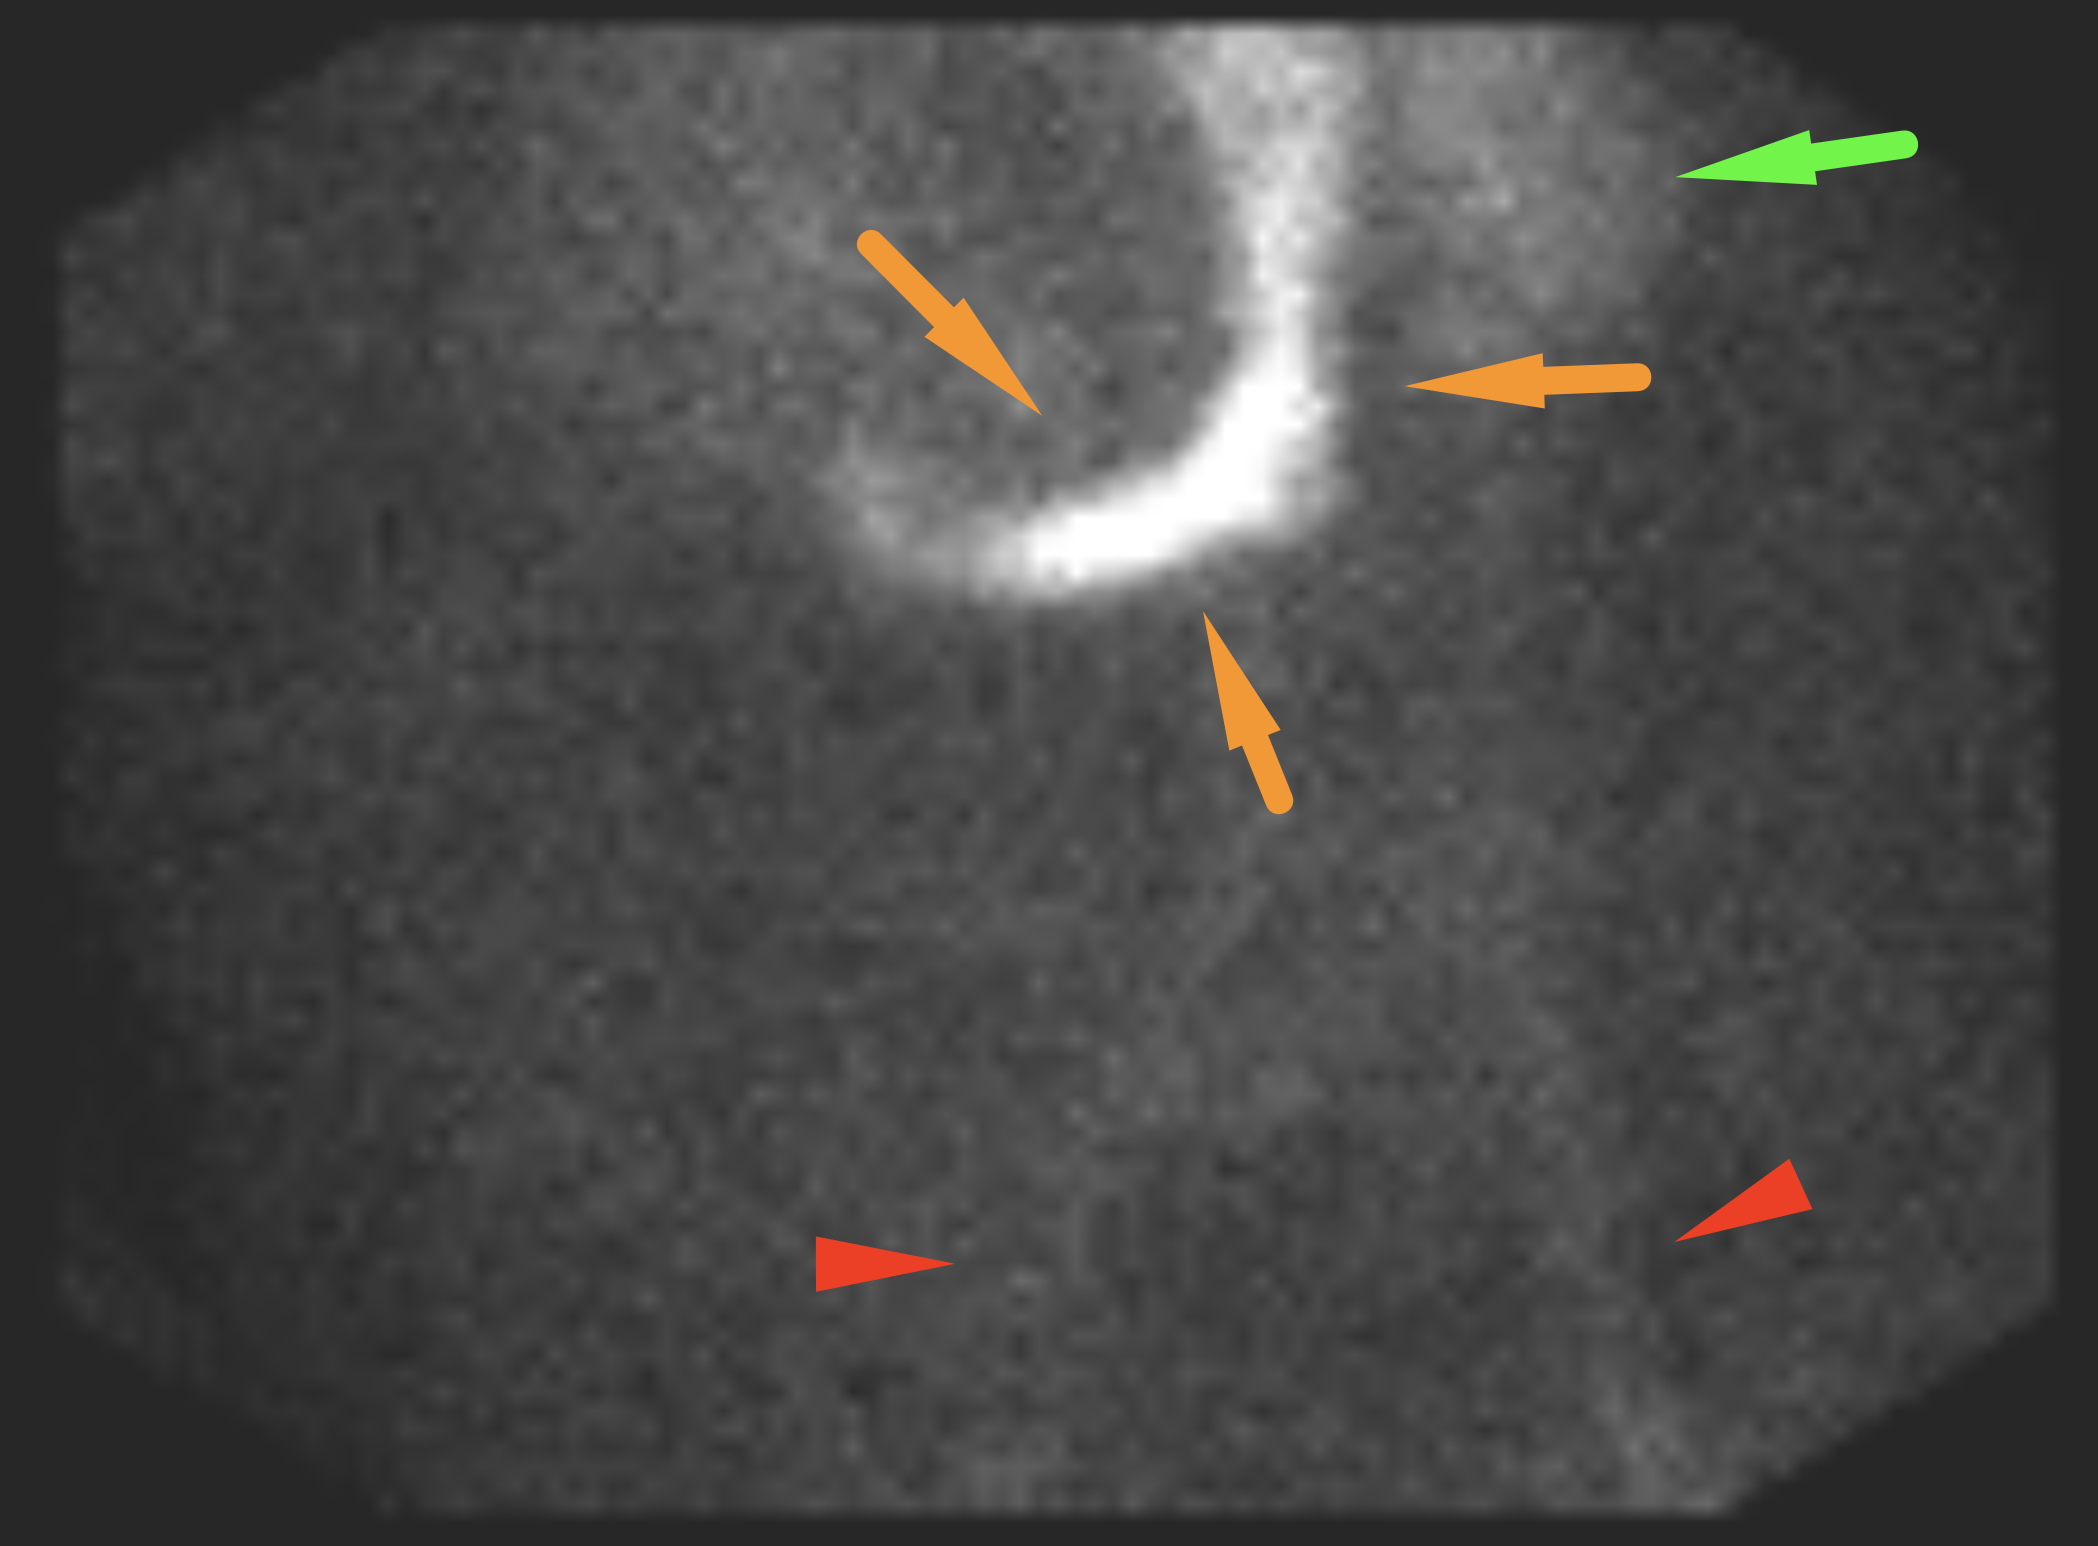

Age: 54

Sex: Male

Indication: Tarry stools, hypotension

Radiotracer: Tc99m labeled RBCs

Sample ReportNo evidence of active GI bleeding during the course of this study.